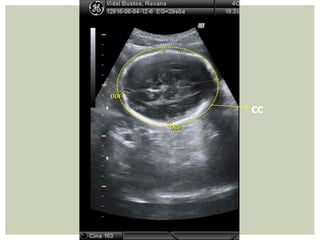

• PERÍMETRO CEFÁLICO (CC): Mejor que DBP para EG, ya

que no se afecta x cambios en morfología craneana. Cálculo

desde lámina externa de calota

CÁLCULO DBP + DOF x 1,57

CC